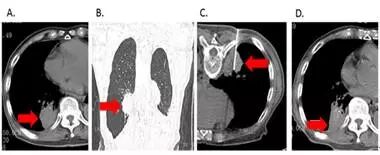

RFA还可以用来姑息性治疗缓解晚期肺癌患者的各种不适症状。(图6)

图6:1例88岁高龄肺癌患者术后复发伴肺内及胸膜转移(图A、B所示),重度疼痛难以入睡。患者经肺肿瘤RFA治疗后疼痛明显缓解,睡眠质量明显改善。一年后随访,患者一般状况良好,肺内肿瘤病灶稳定。